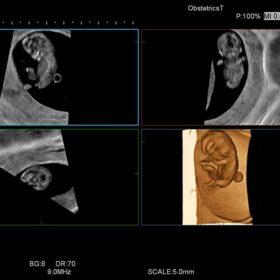

Ultrasound HI VISION Ascendus – Image Gallery and Videos

Obstetrics 4D mode and Urology